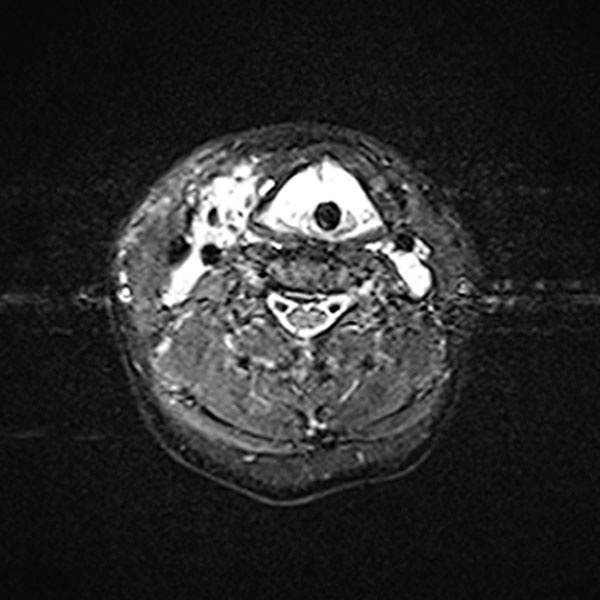

Transverse T2-weighted, fat-suppressed MRI of the neck also shows extensive, grossly hyperintense (white) portions of the venous malformation on the larynx and neck. These obstruct the upper airway. The endotracheal tube is visible in the center.